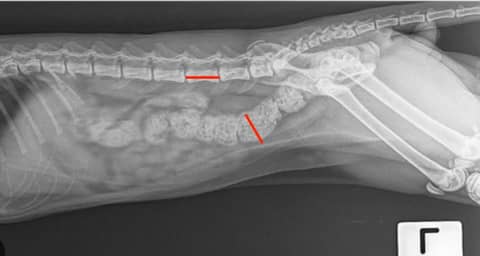

Feline Constipation VS. Megacolon: How Much Poop is Too Much?

From a Science Week Session with Dr Tania Banks.You know when you look at a radiograph of a constipated cat and think, ‘that’s a lot of poop!’? Well, did you know that you can make a good prediction about future outcomes and…